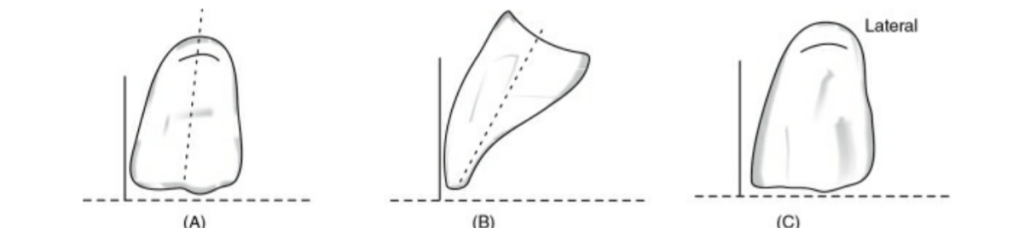

🔻The long axis of the central incisor (the blue line) is positioned parallel to the

vertical axis (the red line) when viewed from the front

Front: Long axis parallel towards the vertical axis.

Side: Slopes labially about 15 degrees.

Occlusal plane: Incisal edge is in contact with occlusal plane

🔻The long axis of the lateral incisor (green line) is placed slightly inclined to

the vertical axis (red line).

Front: Long axis slopes towards midline at incisal edge.

Side: Slopes labially about 20 degrees.

Occlusal plane: Incisal edge is 1 mm short of occlusal plane

🔻The long axis of the maxillary canine (yellow line) should be parallel to the

vertical axis (red line) when viewed from the front.

🔻The long axis of the maxillary canine (yellow line) should be parallel to the

vertical axis (red line) when viewed from the side .

Maxillary canine follows the outline of occlusal rim, and the tip of the canine

corresponds to the canine papillary line

When viewed from:

Front: Long axis parallel towards the vertical axis.

Side: Long axis parallel towards the vertical axis.

Occlusal plane: Cuspid tip is in contact with occlusal plane